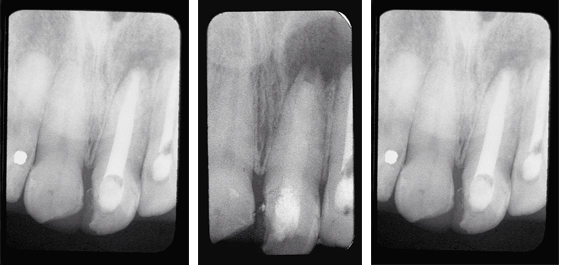

- For complicated cases involving traumatic injury and other instances where extended calcium hydroxide therapy is indicated.

- Treats periapical lesions, abscesses, traumatic injuries, root resorption, root perforations, and weeping canals

- Stimulates apexification and apexogenesis